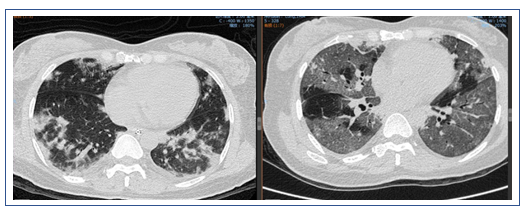

经过治疗后,该患者的氧合有所改善,胸部CT提示肺部磨玻璃影明显吸收,但斑片状实变影愈加明显。此外,还出现了少量的胸腔积液。所以还是考虑患者有无潜在的血管炎或结缔组织疾病。由于患者的血管病变比较突出,D-二聚体和肿瘤标志物水平升高。所以暂时不能除外淋巴瘤或血管相关肿瘤。此时可以考虑行支气管肺泡灌洗,同时取标本送病理检查。

该患者经过短期治疗后,肺部磨玻璃影明显吸收。这种效果应是来源于糖皮质激素的作用。除了血管炎是否也要考虑皮肌炎的可能,可以做皮肌炎抗体检查。另外,建议患者行支气管肺泡灌洗和NGS检查。患者胸部CT显示双下肺背段有斑片影,这或许与患者机械通气时间长有关,可能为重力依赖区斑片渗出影。

患者1月4-6日使用激素,然后停用,胸部CT显示部分病变加重,部分病变被吸收;另外,中下肺背部实变比较明显,而且气管和支气管征比较突出,另外,病变沿着气管、支气管束的分布,符合机化性肺炎表现。但是机化性肺炎不能引起类似呼吸衰竭如此严重的情况,所以个人考虑是否为纤维素性机化性肺炎(AFOP),当然需要病理诊断来进一步明确。患者淋巴细胞非常低,这是目前很难解释的,所以还是期待进一步的检查。

该患者的实变处于整个重力依赖区,从双上肺的后段到下面的背段。一方面可能是停用激素后的反弹,另外一方面考虑跨肺压过小,与长期仰卧位机械通气有关,另外,PEEP过高对患者也有不良影响。此类患者如果不用激素,可以考虑俯卧位通气,能够短期迅速缓解患者重力依赖区的实变。我们还是期待后续的检查结果。